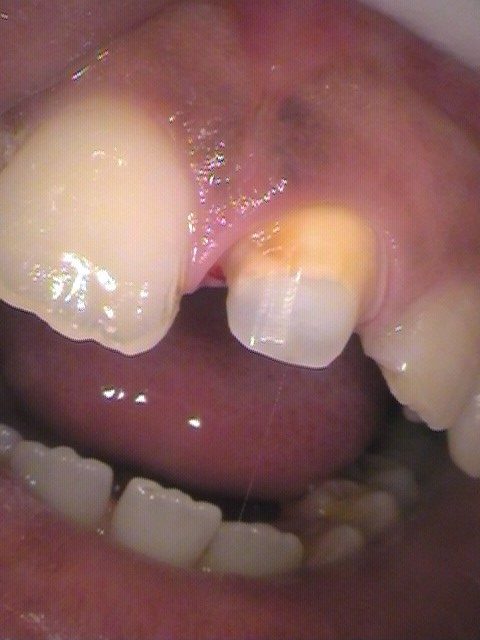

メタルコアも外してみると、根管が見えます。お薬が詰めてあります。

金属のメタルコアを、金属の使わないファイバーコアに変えます。

ファイバーコアを根管に埋め込み、レジンで埋め固めます。

支台築造(しだいちくぞう)と言って、クラウンを被せられるように土台を建てていきます。

形を整えた状態です。

ひとまわり小さく山型に形を整えます。

ここに後に製作したセラミックのクラウン(人工歯)をセットしていきます。